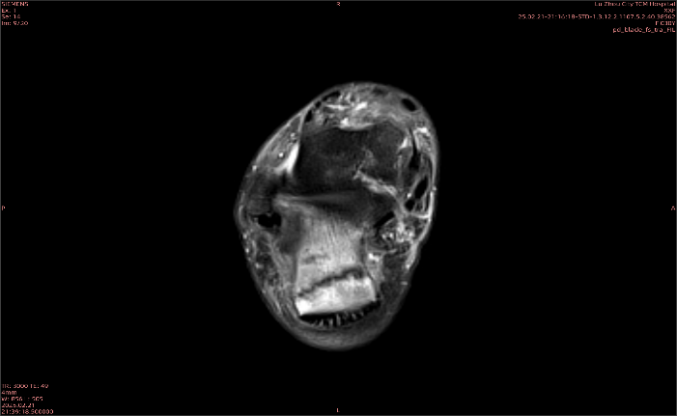

隱性骨折在MRI表現(xiàn)為T1WI序列上見由關(guān)節(jié)面向骨干走行的形態(tài)各異低信號區(qū),有線狀、條狀、紊亂低信號,信號強(qiáng)度不均勻。與T1WI低信號改變相對應(yīng)部位在T2WI上表現(xiàn)為相應(yīng)形狀的高、低混雜信號,且部分低信號周圍可見高信號水腫改變。STIR序列圖像上病灶呈顯著高信號,與信號被抑制的臨近正常骨髓形成鮮明對比,分界也較T2WI成像更為清楚。脂肪組織抑制技術(shù)是MRI的一個(gè)重要性能,脂肪抑制技術(shù)在MRI應(yīng)用中可以改善組織對比和增加病變顯示機(jī)會,這樣骨髓的脂肪抑制后就不會有任何信號,而隱性骨折線及骨髓水腫的異常高信號就會更加明顯的顯示出來。

舉例圖像

圖2

專業(yè)解釋看不懂沒關(guān)系,大家看圖1和圖2就可以了,這是同一個(gè)患者跟骨的磁共振和CT圖像,圖1的紅色箭頭指示的黑線就是磁共振圖像顯示的骨折線,一目了然。而對比圖2的CT圖像上并未顯示異常。